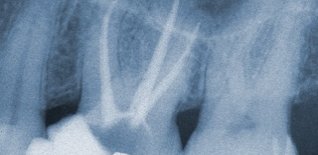

È quella branca dellʼodontoiatria che studia le comunemente dette devitalizzazioni: questo è il punto di partenza principale della maggior parte dei piani di trattamento protesici sui denti naturali ed è quindi estremamente importante una corretta esecuzione nei tempi e nelle tecniche per la durata a lungo termine del trattamento protesico finale.

Anche in questo settore la tecnologia dà una mano con nuove strumentazioni, quali i rivelatori apicali e le strumentazioni meccaniche (non più solo manuali) per ottenere i tre punti fondamentali per il successo: detersione, sagomatura e chiusura tridimensionale del canale.